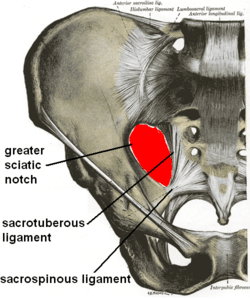

Articulations of pelvis, anterior view, with greater sciatic foramen (labeled in red) and its boundaries. | |